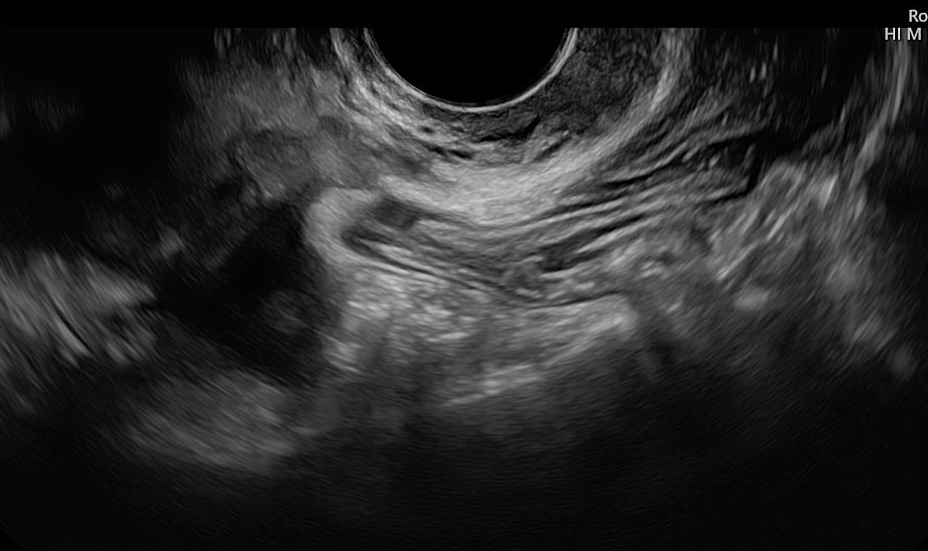

4

Ultrasound image of focal adenomyosis with a hypoechogenic nodule in the posterior outer myometrium, adherent to the distal bowel.